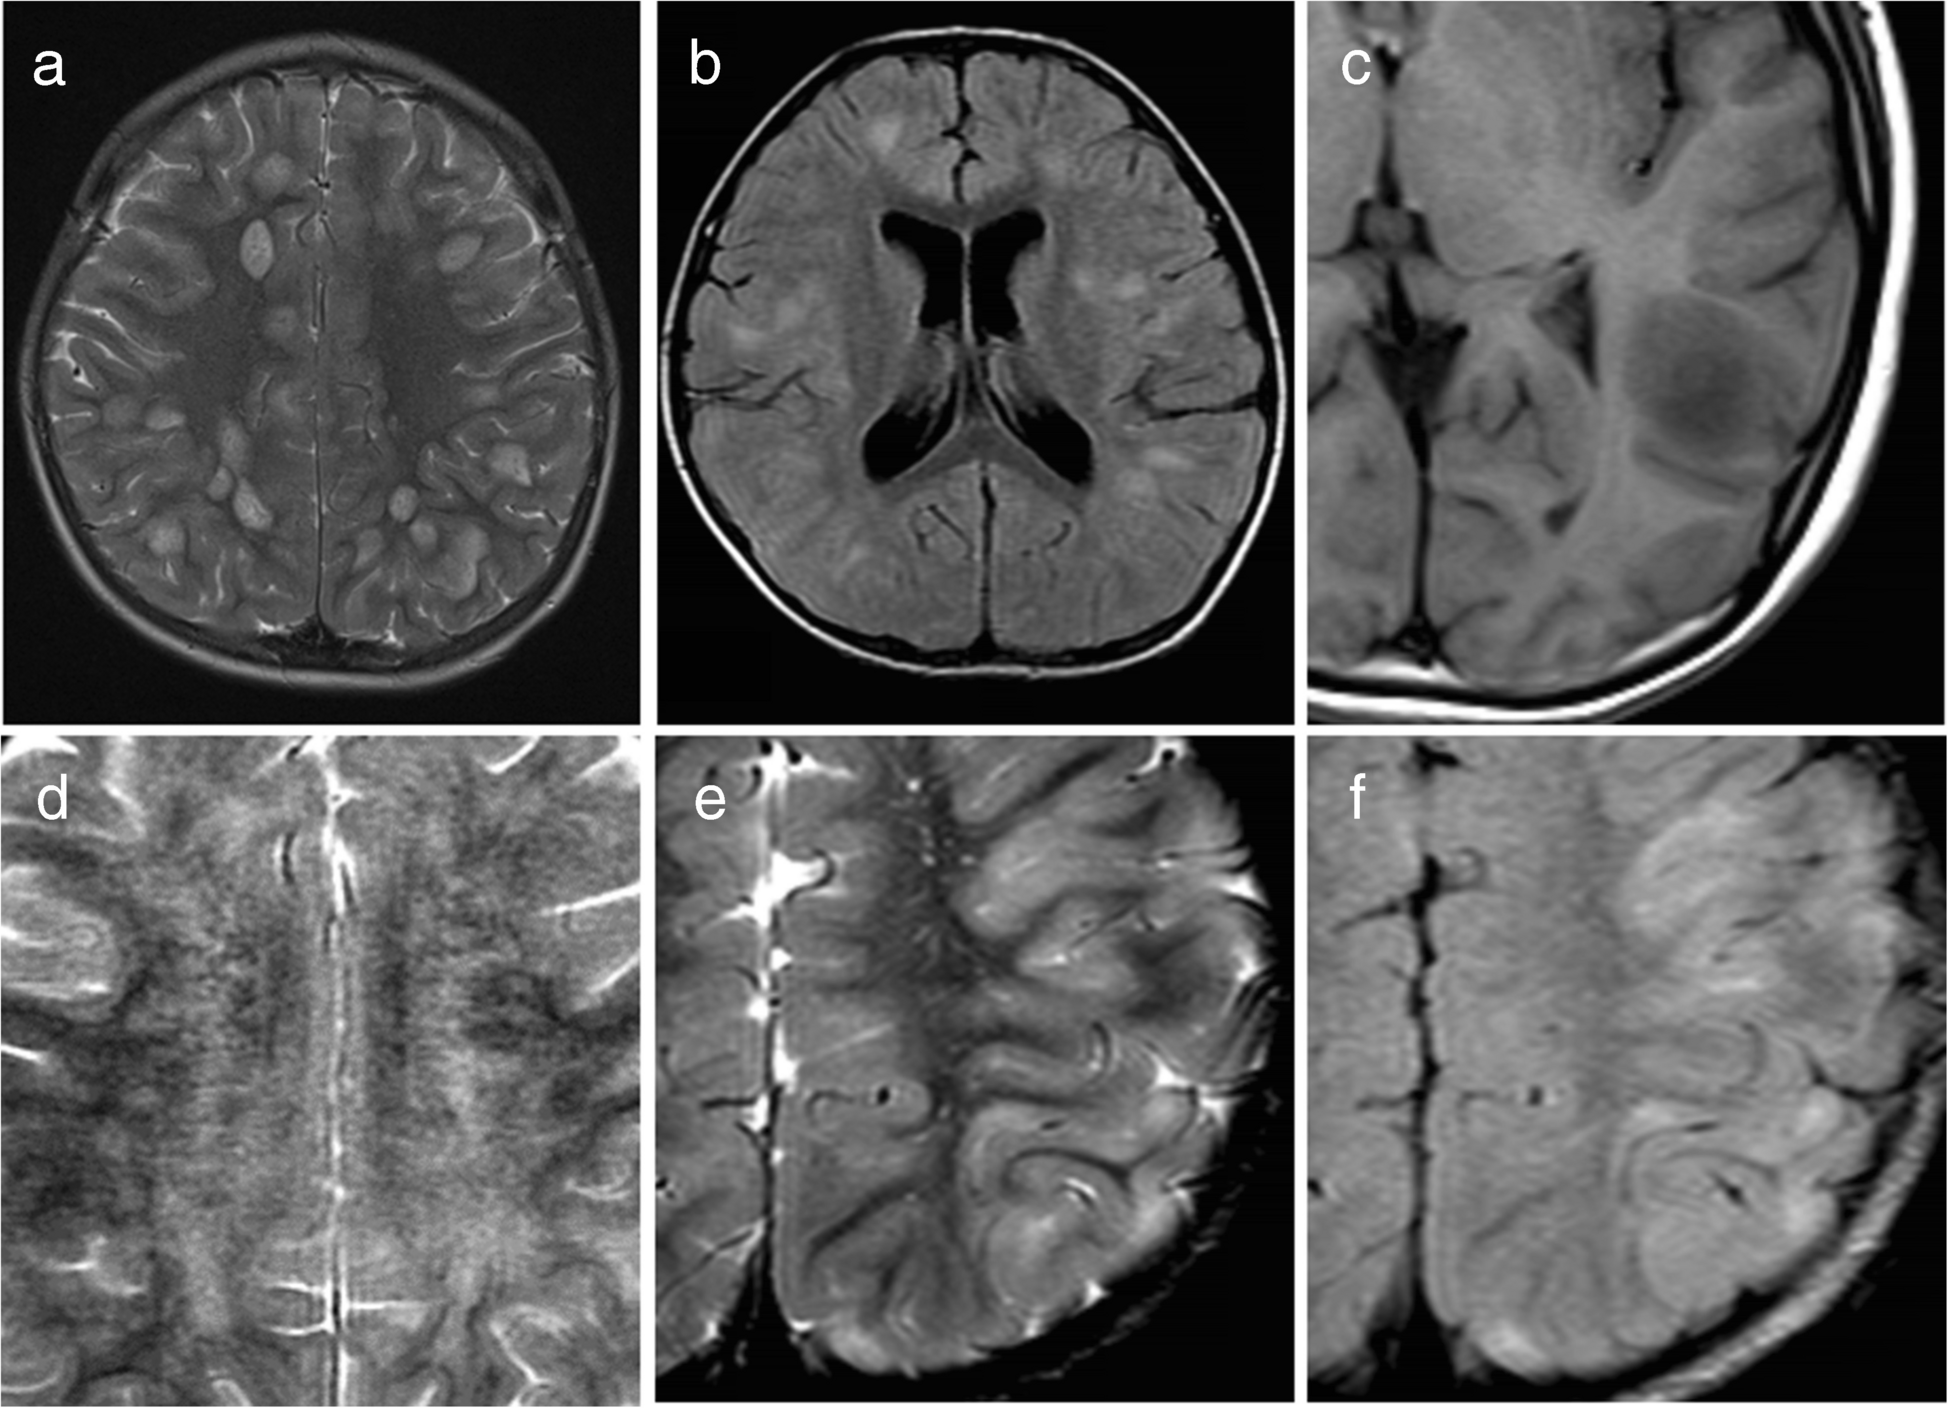

Typical ADEM on brain MRI was defined by the presence of bilateral, diffuse, poorly demarcated, large (> 1–2 cm) confluent lesions primarily affecting the cerebral white matter (Fig. 1) [23]. The following imaging features were considered atypical for ADEM [24]: unilateral lesions, well-defined lesions, exclusively small lesions (all < 2 cm), T1-hypointense lesions, lesions oriented perpendicular to the ventricles, lesions predominantly affecting the subcortical white matter more than the periventricular or deep white matter, and definite cortical involvement (Fig. 2). T1-hypointense lesions were defined as those appearing hypointense compared to gray matter on T1-weighted imaging. When evaluating lesion size, confluent lesions were regarded as large even if composed of multiple smaller aggregating lesions. Subcortical white matter lesions with suspected involvement of the adjacent cortex were not classified as cortical lesions.

Fig. 1

Typical acute disseminated encephalomyelitis (ADEM). Typical ADEM was characterized by bilateral, diffuse, poorly demarcated, large (> 1–2 cm) confluent lesions primarily affecting the cerebral white matter. a Axial fluid-attenuated inversion recovery image from a 5-year-old girl with myelin oligodendrocyte glycoprotein antibody-associated acute disseminated encephalomyelitis (MOG-ADEM) demonstrates bilateral, diffuse, large confluent white matter lesions. b Axial fluid-attenuated inversion recovery image from a 6-year-old boy with MOG-ADEM shows a similar pattern of bilateral, diffuse, confluent white matter lesions, although the margins are less distinct compared to those in (a)